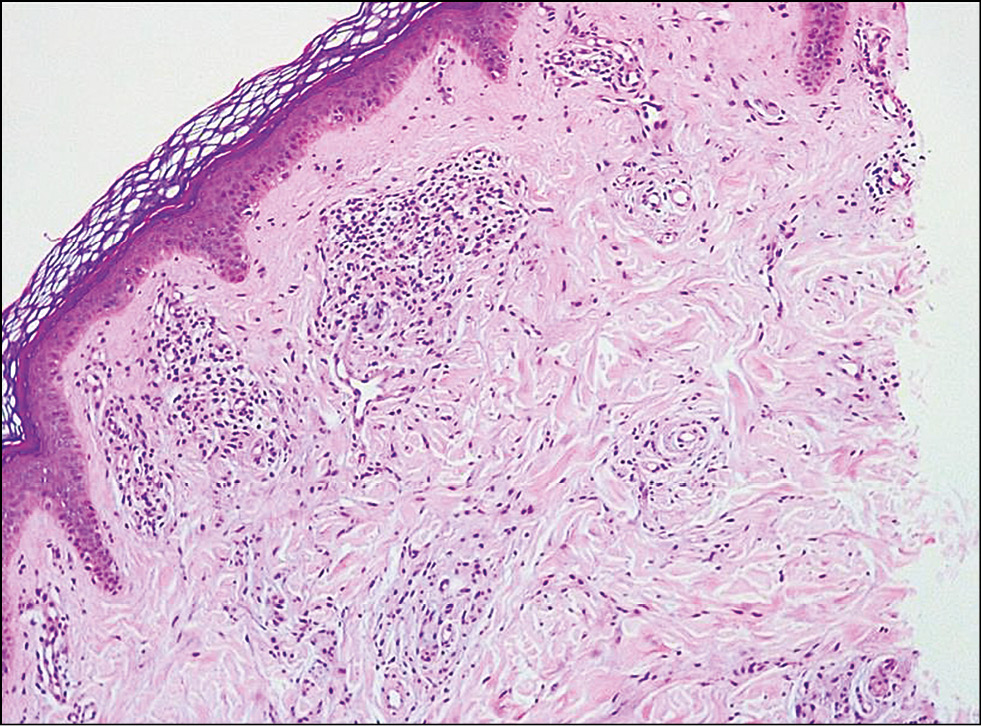

По результатам гистологического исследования диагноз «Ограниченная склеродермия» был поставлен 40 пациентам из 77 на основании патогномоничных признаков: утолщение и гомогенизация коллагеновых волокон в сосочковом слое дермы, периваскулярный гетерогенный инфильтрат из гистиоцитов, лимфоцитов и плазмоцитов, гипоплазия/аплазия эккринных и апокринных желёз, а также волосяных фолликулов (рис. 6). Все 40 пациентов с диагнозом ограниченной склеродермии составили первую исследовательскую группу, куда вошли 35 женщин и 5 мужчин, средний возраст которых составил 28,1±5 лет.

Рис. 6. Диагноз «Морфеа»: в эпидермисе изменения не наблюдаются; в дерме ― утолщение и гомогенизация коллагеновых волокон в сосочковом и сетчатом слоях, периваскулярный гетерогенный инфильтрат из гистиоцитов, лимфоцитов и плазмоцитов, гипоплазия/аплазия эккринных и апокринных желёз, а также волосяных фолликулов. Окраска гематоксилином и эозином. ×100. / Fig. 6. The diagnosis is morphea. There is no pathologic changes in the epidermis. There is a thickening and homogenization of collagen fibers in papillar and reticular dermis; perivascular heterogeneous infiltrtrate consisting of lymphocytes, histiocytes and plasmocytes; hypoplasia/aplasia of apocrine and eccrine glands and hair follicles. (Hematoxylin & Eosin staining, ×100).